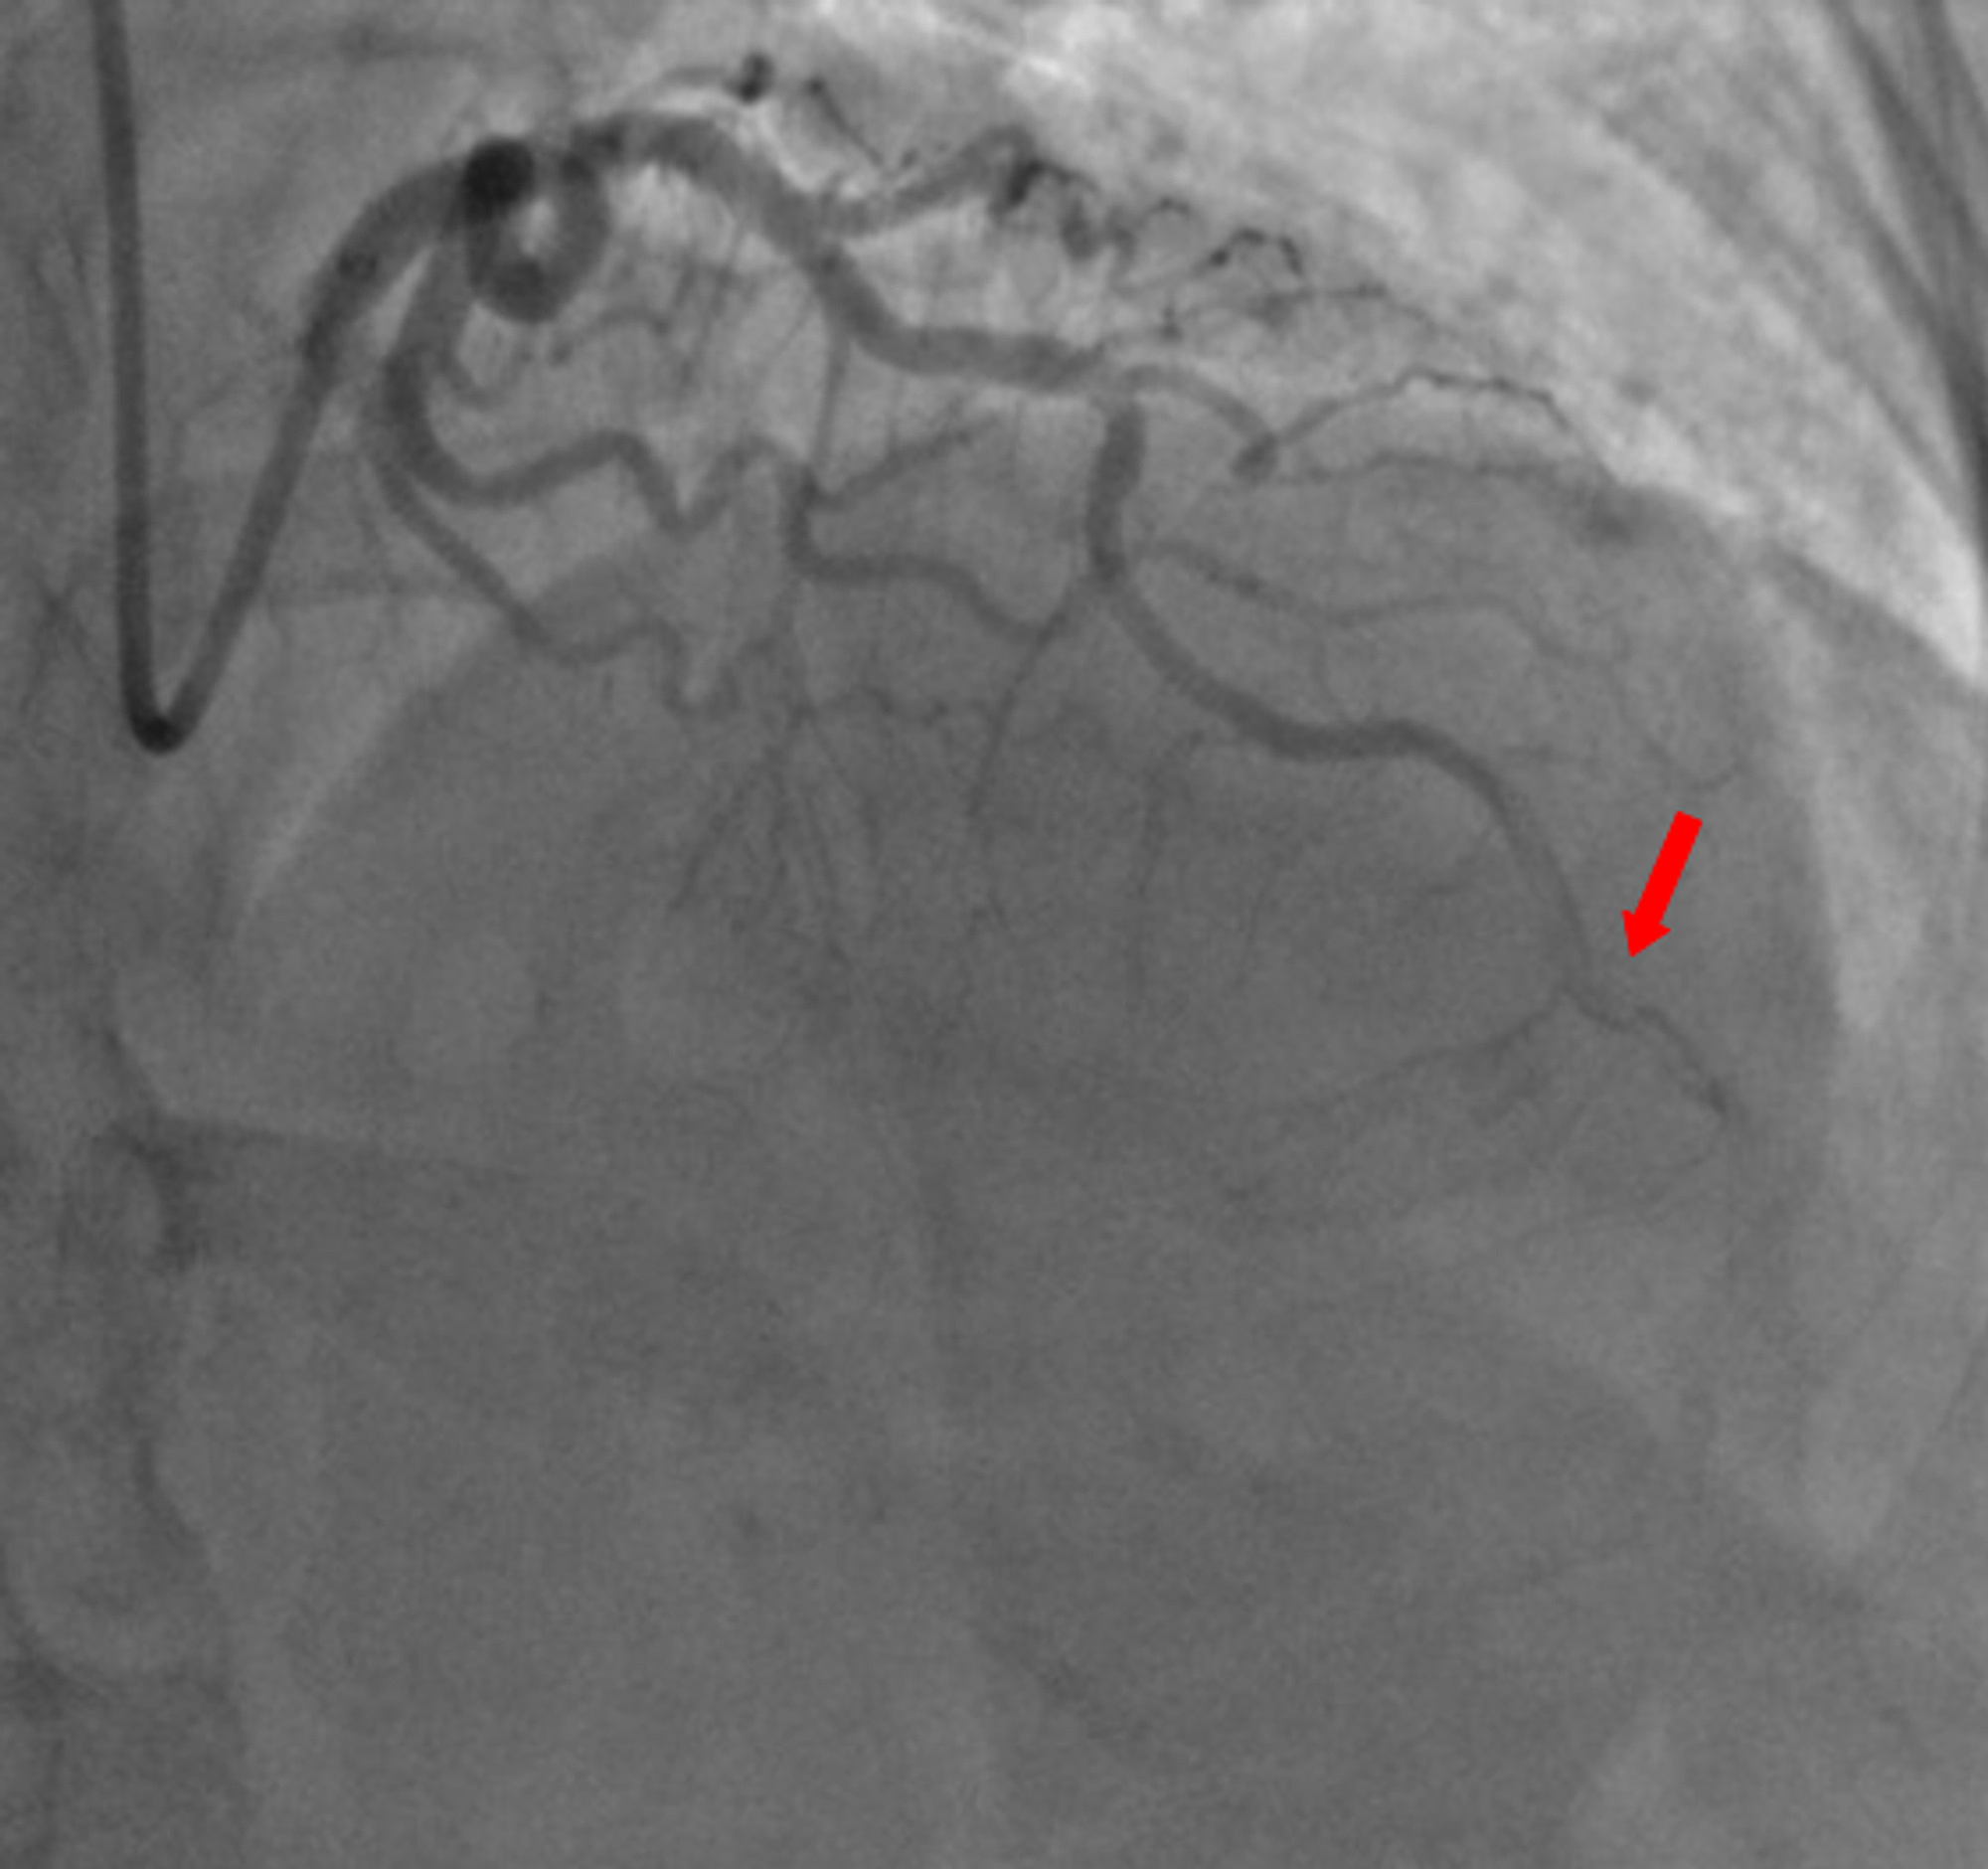

A 59-year-old woman was admitted to the emergency department with sudden onset of chest pain for five hours. She had hypertension (treated with β-blockers) as a cardiovascular risk factor. She was diagnosed with advanced non-small-cell lung cancer with liver metastases one month previously. The patient was not considered for surgical resection, she was scheduled for chemotherapy, and, consequently, no antineoplastic treatment had been initiated yet. Prophylactic anticoagulation was not indicated On clinical examination, her blood pressure was 150/90 mmHg with a pulse of 100 beats per minute, oxygen saturation of 95%, and normal heart sounds. The 12-lead electrocardiogram showed sinus rhythm with a heart rate of 102 beats for minutes and ST-segment elevation in all leads except aVR where ST-segment depression was noted (Figure 1). Her laboratory test results revealed a baseline troponin T level of 1212 ng/ml (normal range < 26 ng/ml). Also, the echocardiography findings revealed akinetic walls from the mid to apical septum and anterior and inferior walls. The ejection fraction was estimated to be 39%. Therapy was started with clopidogrel, aspirin, and low-molecular-weight heparin. The patient underwent a coronary angiogram from the right radial approach, which revealed the presence of an extended thrombus in the left anterior descending artery (LAD), and another thrombus was found in the second segment of the right coronary artery (RCA) with thrombolysis in myocardial ischemia (TIMI) III flow and without any atherosclerotic lesions in the coronary artery tree (Figure 2 and Figure 3), therefore, balloon angioplasty and/or stent placement was not considered. The patient was taken to the coronary care unit (CCU) and tirofiban infusion was administered for a period of 48 hours. In view of persistent breathlessness, pulmonary embolism was suspected. There were no symptoms or clinical signs suggestive of deep venous thrombosis. A computed tomographic pulmonary angiography was performed and showed a distal pulmonary embolism (Figure 4). The patient was discharged on acenocoumarol to be followed as an outpatient. At her 45 days follow-up, she did not report any episode of chest pain, bleeding, as well as any thrombotic events.